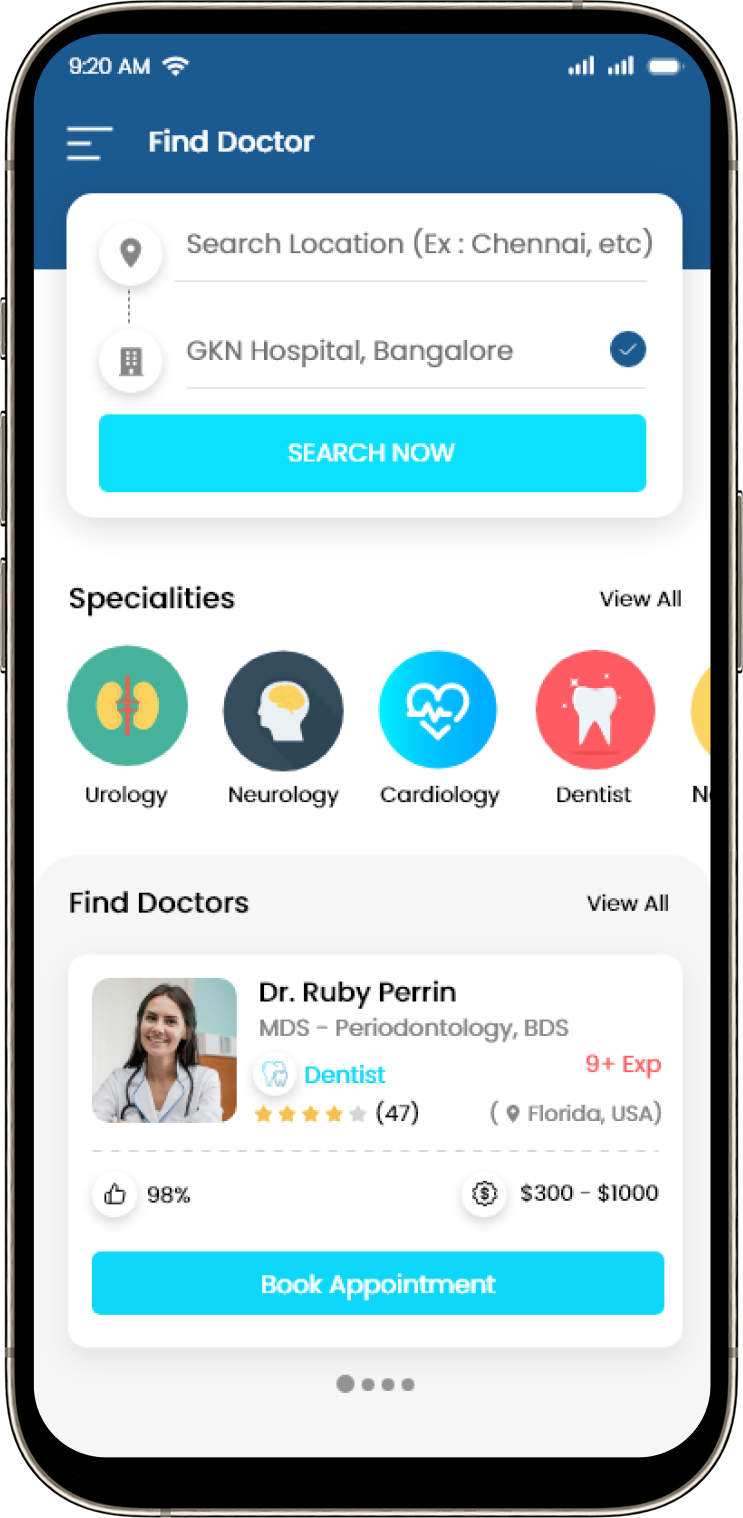

Get exclusive discounts, wallet cashback, personalized reminders, and fast re-order options only on our mobile app. Health meets convenience.